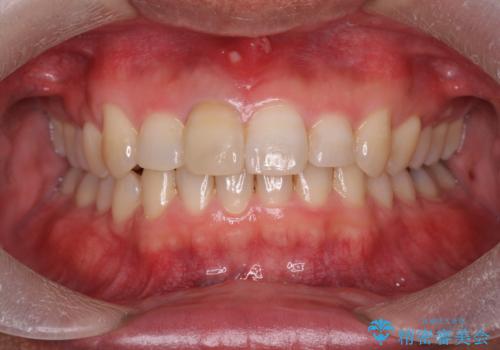

深い噛み合わせと上顎前突の状態を治すのに時間がかかりましたが、治療後は理想的で安定した咬合関係となりました。

- 前歯のがたつきを改善したい、と矯正治療を希望され来院されました。

・深い噛み合わせ(ディープバイト) ・2級性の咬合関係(上顎前突)・前歯のがたつき